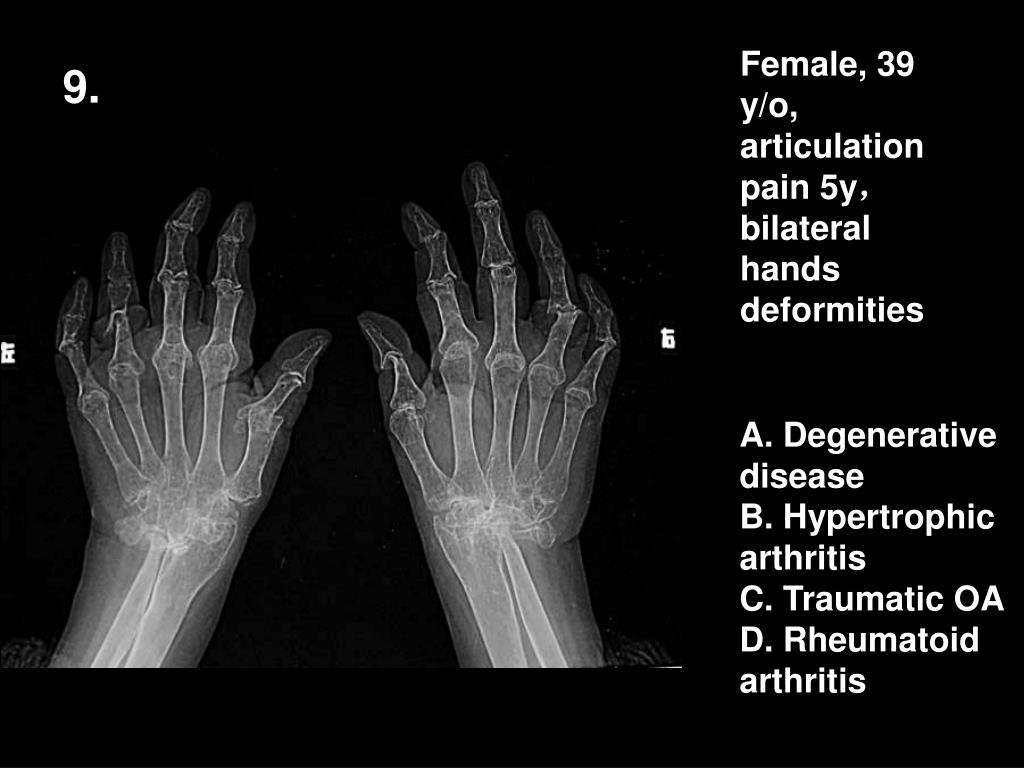

10. Female, 39 y/o, articulation pain 5y,bilateral hands deformities 9. A. Degenerative disease B. Hypertrophic arthritis C. Traumatic OA D. Rheumatoid arthritis